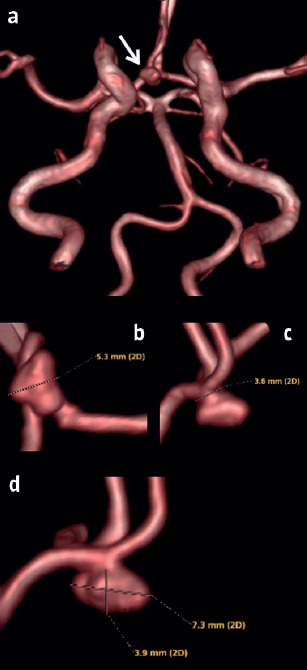

Hemorrhagic adenoma mimicking anterior communicating artery aneurysm.